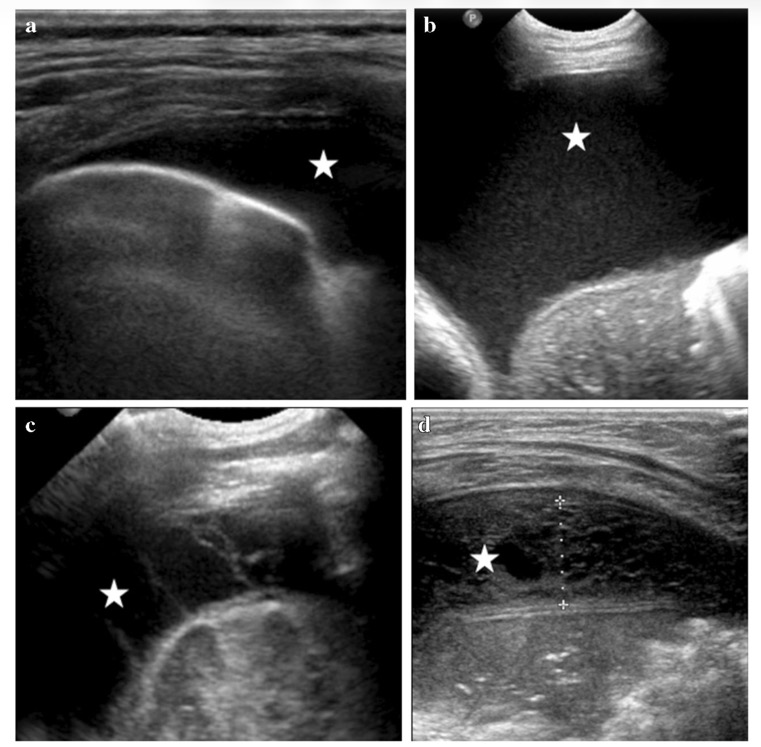

Patterns échographiques d'épanchement pleural:

(a) épanchement pleural anéchoïque: transudat

(b) épanchement pleural non cloisonné complexe: exsudat (lempyème pleural)

(c) épanchement pleural cloisonné complexe: (empyème fibrinopurulent)

(d) épanchement échogène avec des septa hétérogènes: (fibroblastes, organisation chronique de l'empyème)